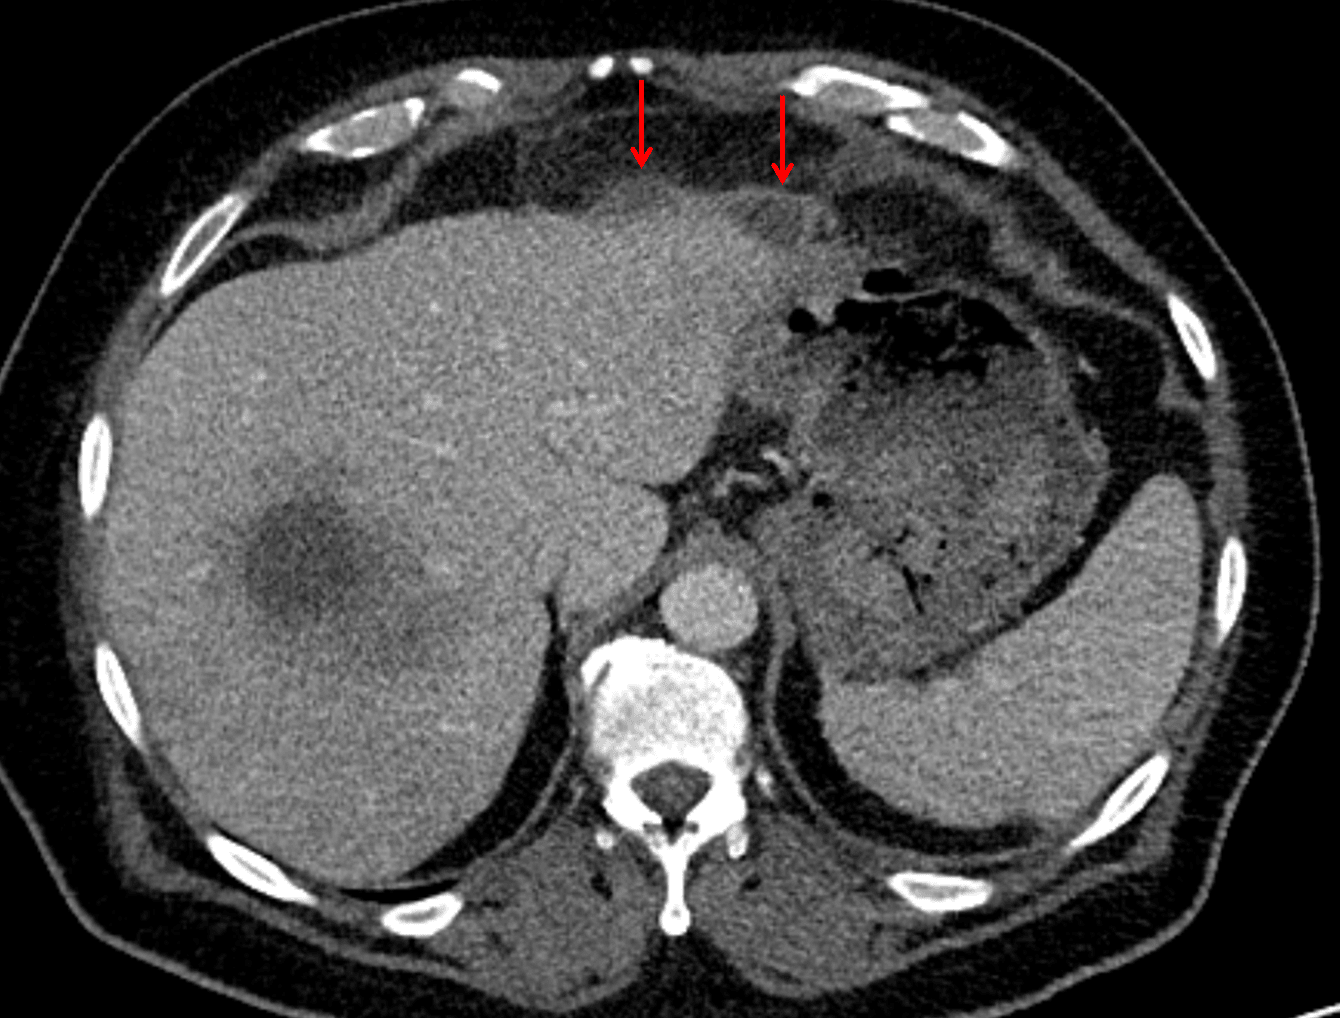

- Peripherally enhancing subcapsular collections along the anterior margin of the left hepatic lobe (collection 1, collection 2) measuring 3 x 1 cm and 2 x 1 cm

Red arrows: additional smaller subcapsular abscesses.